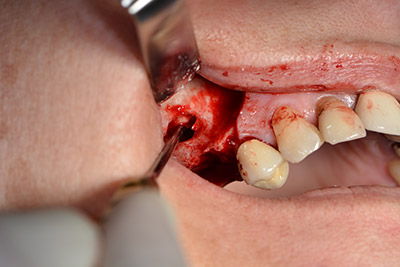

L'incisione classica (rilascio crestale e buccale) e la preparazione del lembo mucoperiosteo favoriscono un'ottima panoramica.

Dunque, l'impianto viene posizionato e l'osso ricostruito. In questo caso, considerate le dimensioni della regione di accrescimento, i microframmenti dell'osso autologo (raccolti con un'apposita cannula di aspirazione in seguito alla perforazione dell'impianto 16 e della fenestrazione 14) vengono combinati con dei materiali di riempimento dell'osso.

Una membrana riassorbibile viene usata come barriera in direzione buccale per contenere l'accrescimento. Infine, vengono applicate suture resistenti alla saliva (da fig. 15 a 19).